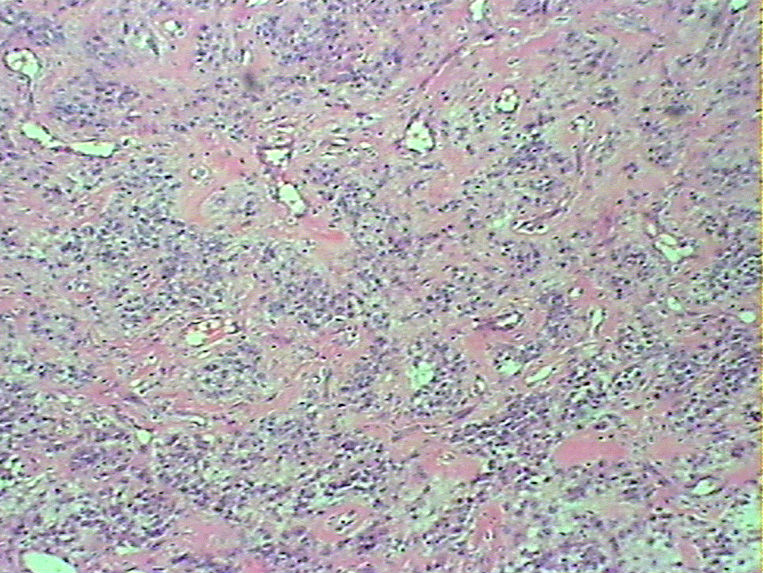

腹部肿物会诊血管球瘤

女45发现下腹部皮下肿物4个月

灰白色肿物一枚,9*8*5cm,切面实性、质韧,似有包膜

• 腹部肿物会诊血管球瘤图2

图2

血管球瘤